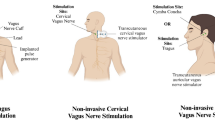

The occurrence and development of CNS diseases are usually accompanied by inflammation [15]. Excessive inflammatory responses can promote the death of neurons and glial cells, leading to an aggravation of the condition [16]. The vagus nerve is known as a homeostatic component in the anti-inflammatory loop along the gut–brain axis. For example, in research focused on inflammatory bowel disease, VNS has been shown to regulate the intestinal inflammatory response. Chronic VNS (1 mA, 5 Hz, pulse width of 500 μs) was used to treat Crohn's disease model rats for 5 days in a previous study, which showed that VNS could reduce the extent of body weight loss and levels of inflammatory markers such as tumour necrosis factor-α (TNF-α) and interleukin-1β (IL-1β) [17,18,19]. Additionally, researchers are also applying VNS in the treatment of stroke, brain injury, depression, etc. [20]. As shown in Fig. 1, the results from these studies support the idea that VNS regulates inflammation through different mechanisms, as described below.